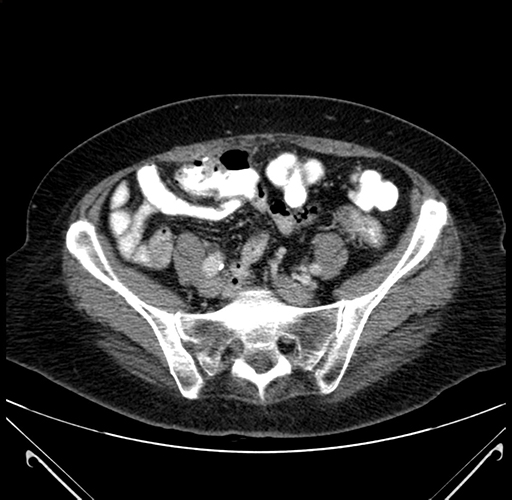

Pre-Chemo: Axial Venous

Axial Venous